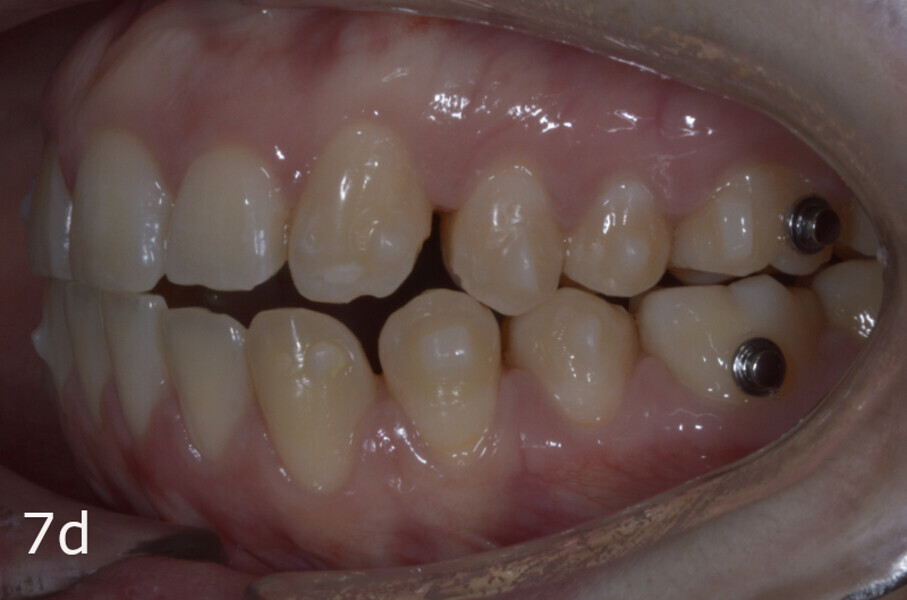

The treatment objectives included closing the anterior open bite, achieving a bilateral Angle Class I relationship and a proper overjet and overbite, correcting the midline discrepancies, and achieving a profile harmonisation. The treatment plan consisted of orthodontic camouflage treatment with asymmetric distalisation in three of the four quadrants using Invisalign aligners (Align Technology) and third molar extraction. The Invisalign Comprehensive package was chosen, and 63 pairs of aligners were used (Figs. 7–10). Each aligner was worn for 20 hours a day for one week each. The use of Class III elastics on both sides was indicated. Afterwards, ten refinement aligners were needed to improve the interdigitation on the right side (Figs. 11 & 12).